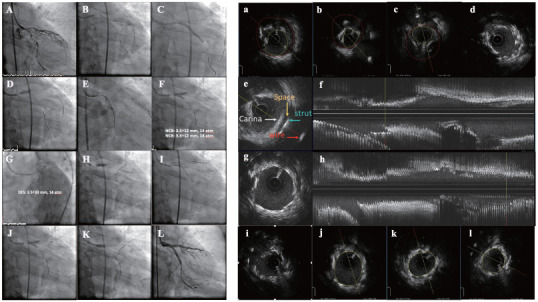

冠状动脉造影被认为是诊断冠状动脉疾病和指导经皮冠状动脉介入治疗(PCI)的金标准。然而,2D投影血管造影术不能完全反映3D冠状动脉管腔。血管内超声(IVUS)可以通过提供更多关于血管内腔尺寸、斑块特征、支架部署和装置故障机制的信息来克服冠状动脉造影的许多局限性。来自观察性研究和随机对照试验的越来越多的数据证实了在PCI期间IVUS指导的临床益处。本文总结了有关IVUS指导的证据,以突出其优势,并支持在PCI期间使用IVUS。

Coronary angiography has been considered the gold standard for the diagnosis of coronary artery disease and guidance of percutaneous coronary intervention (PCI). However, 2D-projection angiography cannot completely reflect the 3D coronary lumen. Intravascular ultrasound (IVUS) can overcome a number of limitations of coronary angiography by providing more information about the dimensions of the vessel lumen, plaque characteristics, stent deployment, and the mechanisms of device failure. Growing data from observational studies and randomized controlled trials have confirmed the clinical benefit of IVUS guidance during PCI. This article summarizes the evidence regarding IVUS guidance to highlight its advantages and to support the use of IVUS during PCI.